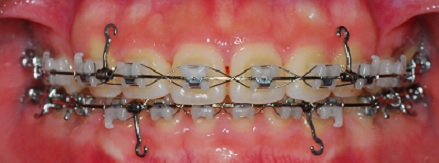

(정면 사진)

치아 상태를 보시고 철사에 걸어놓았던 다리를 앞으로 당기고

앞니에 항상 고무줄을 걸었었는데

이번에는 철사로 감았네요~

철사위에 철사를 감으니 아이언맨이 생각...ㅋㅋㅋㅋ

이번달에는 고무줄을 걸지 않고 앞니에 철사만 달았습니다

철사하나 덧달았을 뿐인데 오랜만에 치아가 많이 아푸네요